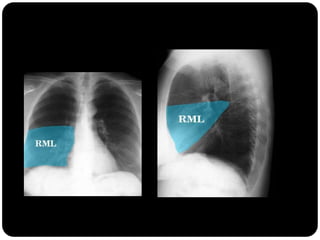

Atelectasia do Lobo Médio

Impacto mínimo

sobre volume total

do hemisfério

direito (é o menor

dos lobos) LS e LI

inferior compensam